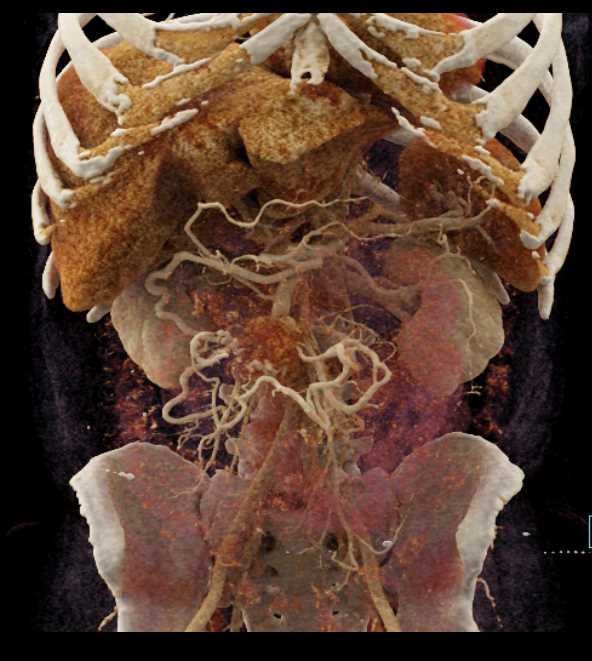

Carcinoid Tumor with Desmoplastic Reaction